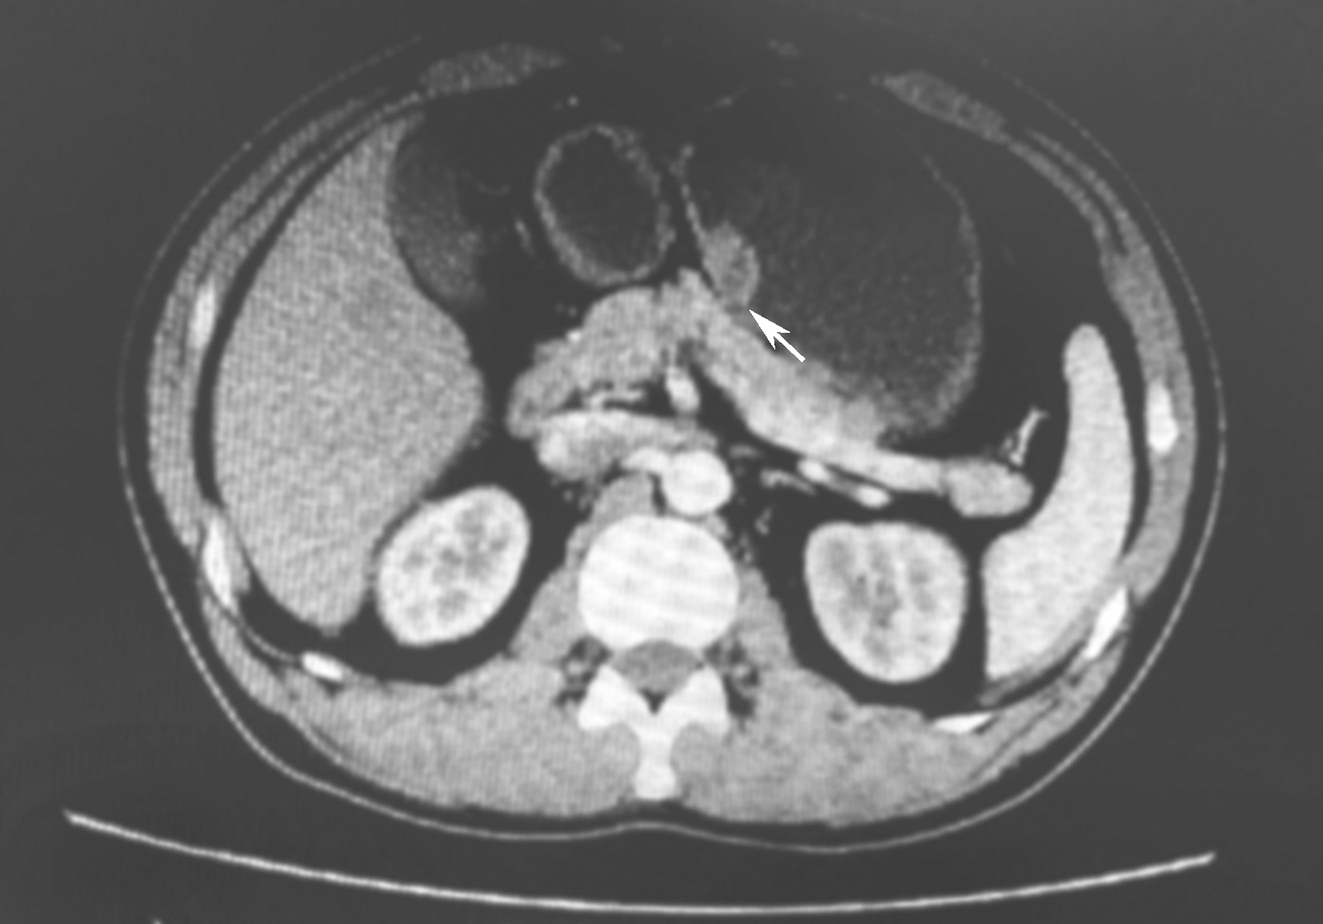

2016年9月行全腹平扫+增强CT示:胃底下部小弯侧隆起肿块影,大小约2.3cm×1.2cm,平扫CT值约50HU,增强后动、静脉期CT值约74、80HU,肿块内密度不均,病变边界清晰,邻近浆膜面光整,周围脂肪间隙清晰,未见明显肿大淋巴结。提示胃肠道间质瘤(gastrointestinal stroma tumor,GIST)可能,余无异常(图1)。

图1 增强CT提示胃底小弯侧隆起肿块